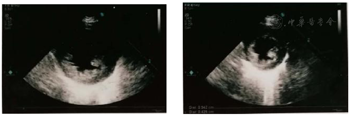

左心室心肌均匀肥厚,左室心尖肌小梁显著增多,左室收缩功能正常范围,左心室射血分数79 %,提示肥厚性心肌病(图1)。